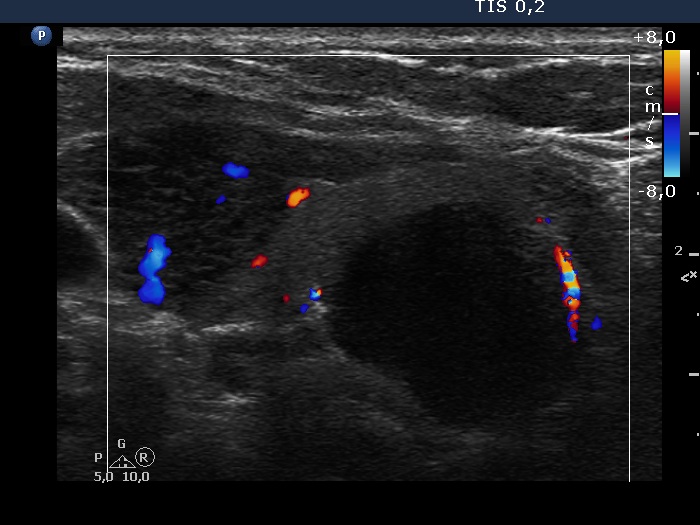

Follow-up investigation 3 years later (ultrasonographic picture 15)

Lower two-third of the left lobe, longitudinal, color Doppler mode. The lowest lesion has no vascularity.